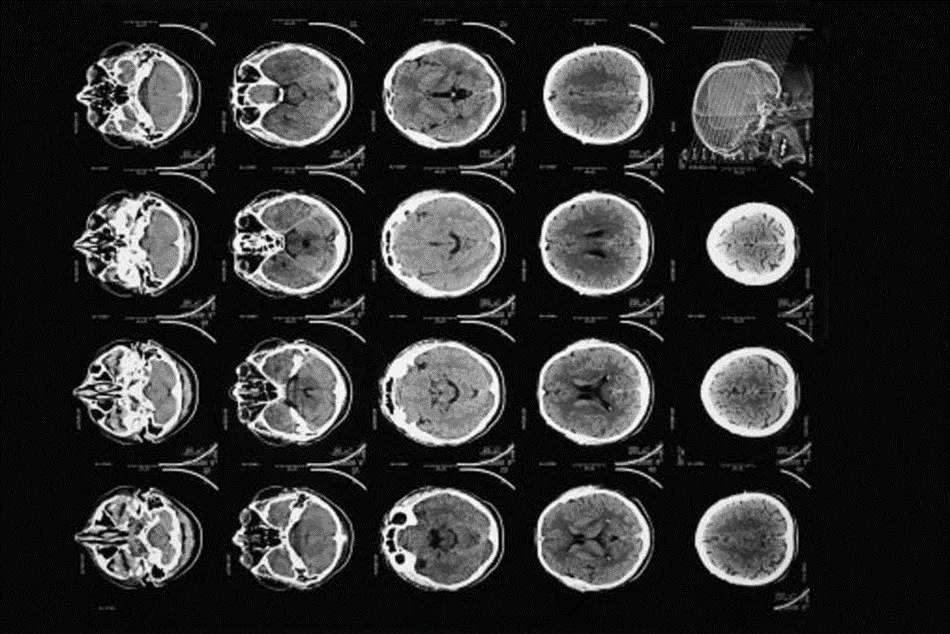

1973年,美國人羅伯特·萊德利(Robert Ledley)發明了一種全身掃描儀,可以對其他器官、血管,當然還有骨骼進行成像。現代掃描儀速度更快、分辨率更高,最重要的是,它的輻射暴露更少。此外,甚至還有移動掃描儀。

現代CT掃描提供了比亨斯菲爾德1971年的原始掃描更高分辨率的大腦“切片”圖像。

截止2020年,美國的技術人員每年進行的掃描超過8000萬次。一些醫生認為這個數字過高,也許其中三分之一是不必要的。雖然這可能是真的,但CT掃描有助於識別腫瘤,並確定是否需要手術,已經使世界各地許多患者的健康受益****。在急診事故後,它們對於快速搜索內傷特別有用。